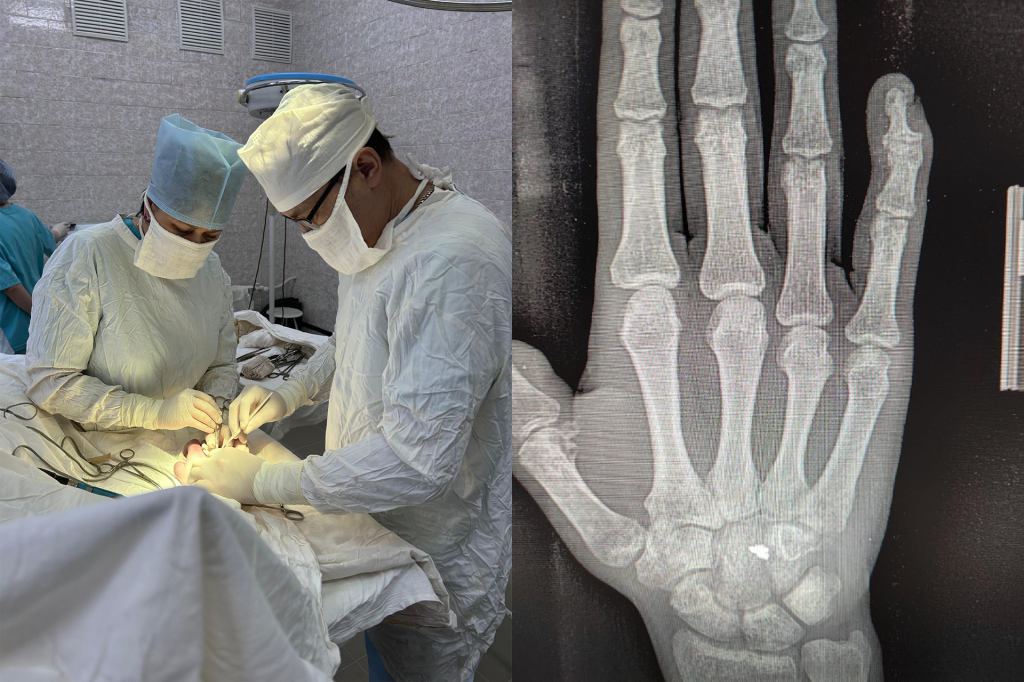

Врачи Верхне-Татышлинской больницы в Башкирии провели успешную операцию по удалению осколка гранаты участнику спецоперации.

Ранение мужчина получил от разорвавшегося всего в нескольких метрах снаряда. Осколок гранаты попал в область сухожилия мышцы разгибателя пальцев. Инородное тело вызывало резкую боль и ограничивала движения кисти.

«Хирурги Верхне-Татышлинской ЦРБ целиком и полностью извлекли осколок. Теперь солдат сможет вернуться к своим боевым обязанностям», — написали в пресс-службе Минздрава.